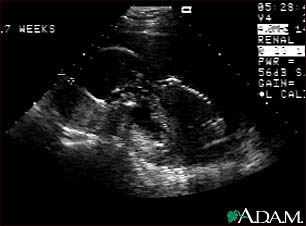

Ultrasound, normal fetus - profile view

This is a normal fetal ultrasound performed at 17 weeks gestation. In the middle of the screen, the profile of the fetus is visible. The outline of the head can be seen in the left middle of the screen with the face down and the body in the fetal position extending to the lower right of the head. The outline of the spine can be seen on the right middle side of the screen.